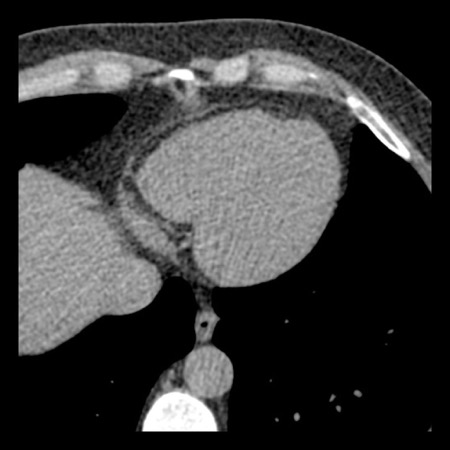

case 1 – CAD-RADS 2/P1

First, scroll through the scan.

Not all images are included. Some images without any abnormalities are skipped

from the series.

How would you describe the findings on the coronary CTA?

The findings are:

- Agatston score of

this patient was 14 (P1). Please, also note the calcification of the aortic valve. - Some partially

calcified and calcified plaques are present in the LAD with mild stenosis

(25-49%). - Calcified-plaque in

the LCX causing minimal stenosis (<25%). - Non-calcified

plaque in the distal RCA causing minimal stenosis (<25%). - This patient classifies

as CAD-RADS 2/P1, which means no further workup is needed.